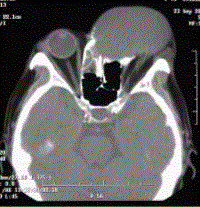

问题 患者男,60岁,头痛,前额部局部隆起。查体:前额隆起处可触及乒乓球样肿块,CT显示如下图。 关于鼻窦黏液囊肿的发生几率,正确的是

选项 A.上颌窦>额窦>筛窦>蝶窦 B.上颌窦>筛窦>蝶窦>额窦 C.额窦>上颌窦>筛窦>蝶窦 D.额窦>蝶窦>上颌窦>筛窦 E.筛窦>额窦>上颌窦>蝶窦 F.上颌窦>额窦>蝶窦>筛窦

答案 E